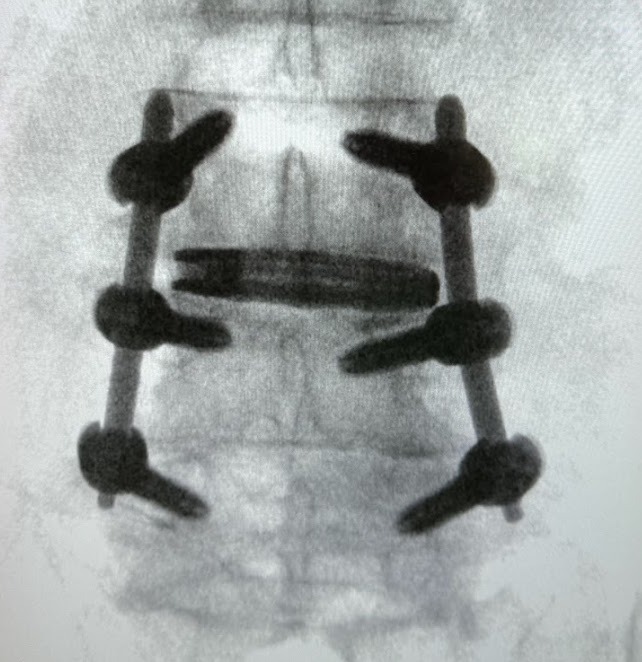

Ortopedia della Colonna Vertebrale